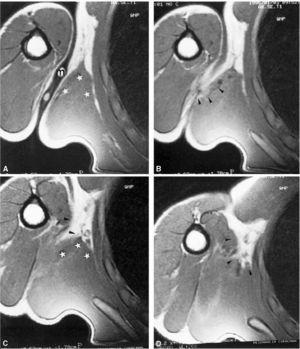

Una nova ressonància magnètica als 12 mesos detecta l'engruiximent de la fàscia de l'LD amb retracció muscular d'aquest. S'hi afegeixen talls axials i coronals en abducció i rotació externa amb la finalitat de posar en tensió l'LD. La reparació fibrosa mostra més retracció de les fibres més distals ­les més laterals­ del múscul (fig. 6). Aquesta retracció produeix l'efecte de destralada i descobreix el tendó nu del TM. A la zona miotendinosa axil·lar s'observa procés cicatricial sense signes d'afectació inflamatòria crònica.

Figura 6 Control amb ressonància magnètica als 12 mesos. Imatge frontal amb el braç en abducció i rotació externa, amb marcador cutani (m). S'identifica una clara seqüela cicatricial (fletxes negres) sense signes d'edema perimuscular i clara retracció en el Latissimus dorsi (asteriscs).